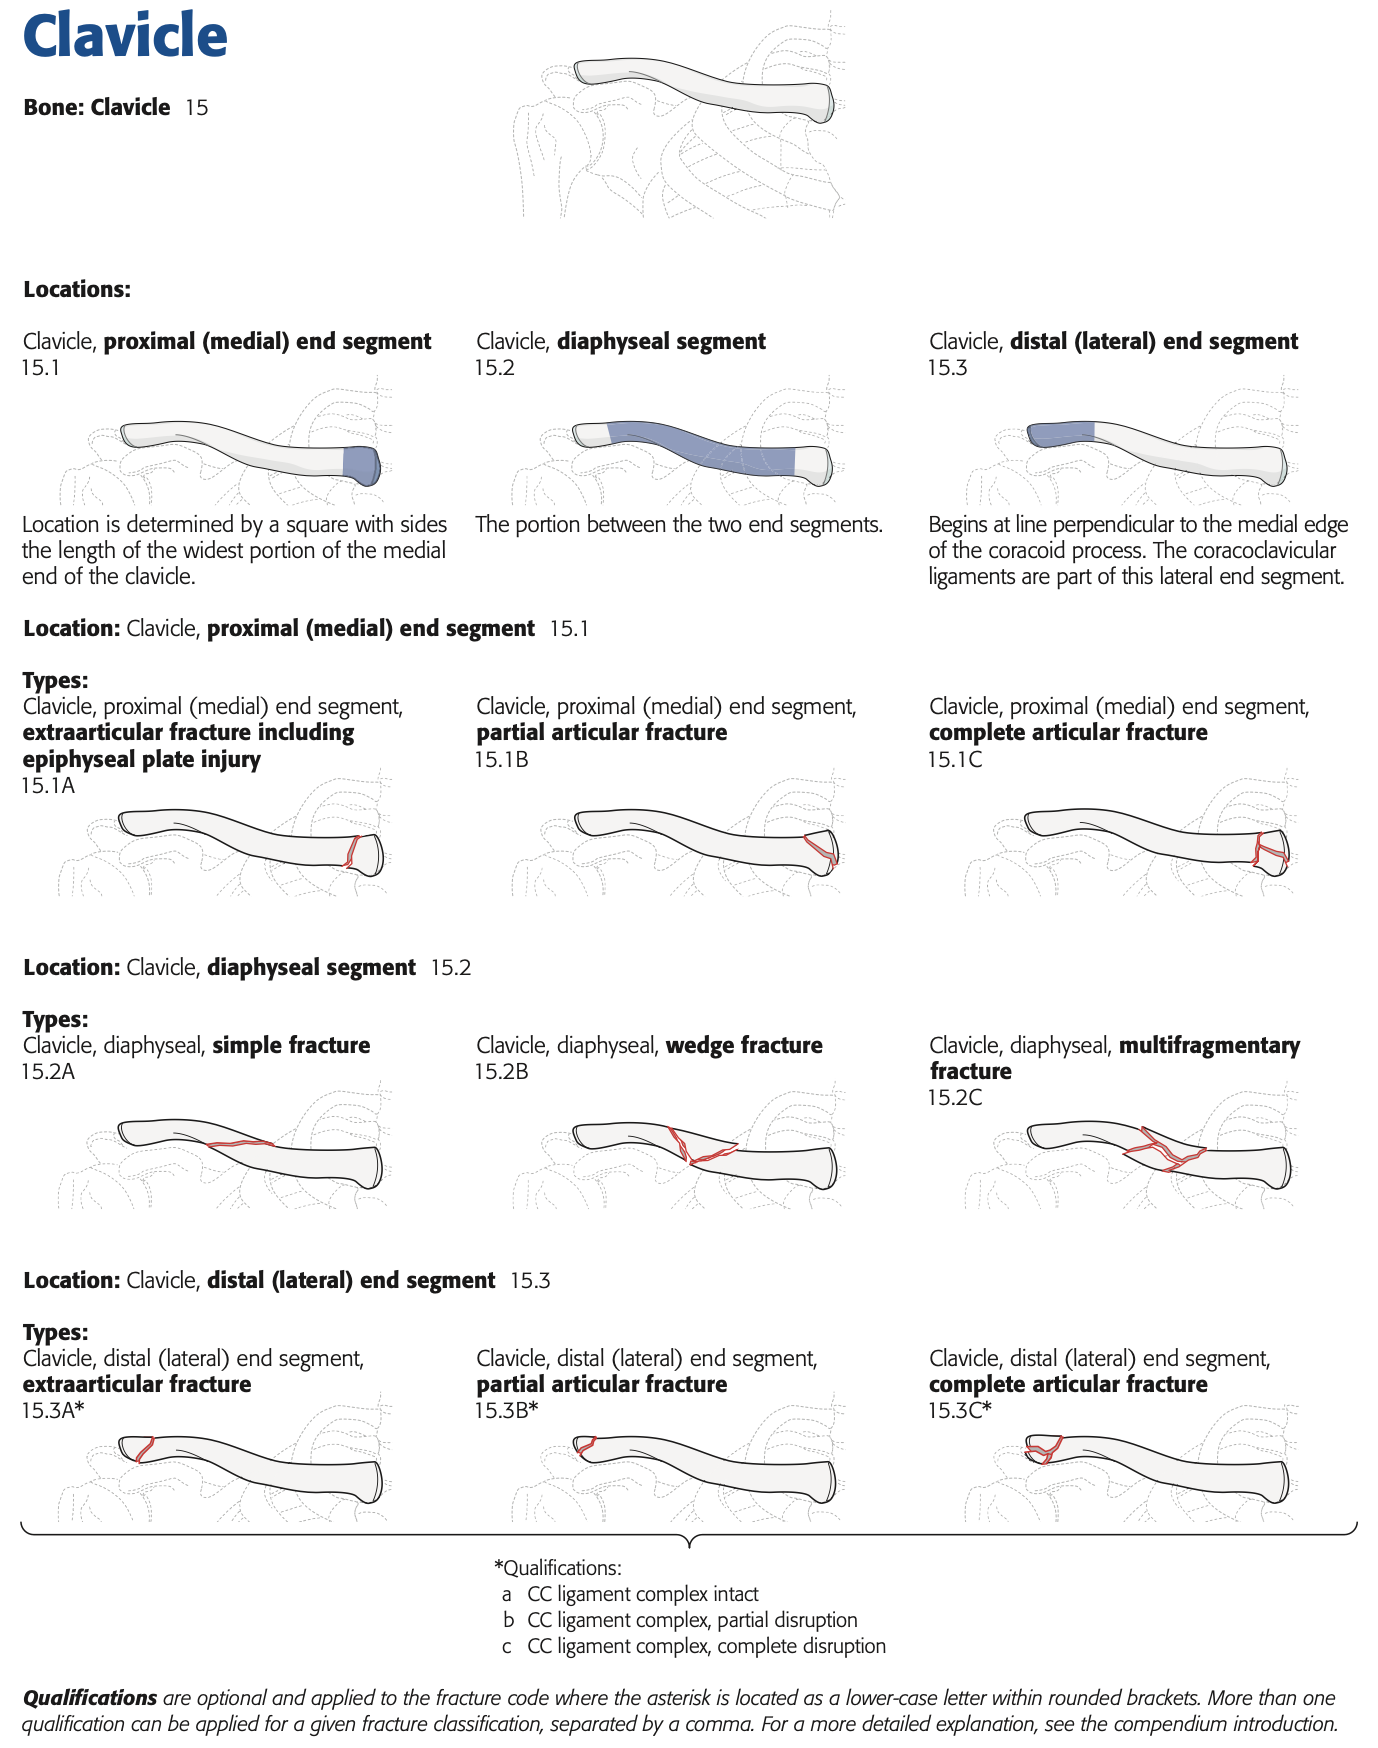

整形外科クリニックの後輩医師から鎖骨骨折の高齢の患者さんが手術を希望されて, 紹介されて受診されました. 飲酒後に転倒されて, 同じ側のあばら骨(肋骨)も3本骨折していました. 鎖骨の骨折は, 中央部で骨のかけら(骨片こっぺん)を生じた骨折で, AO/OTA分類では15.2Bでした(上図参照).